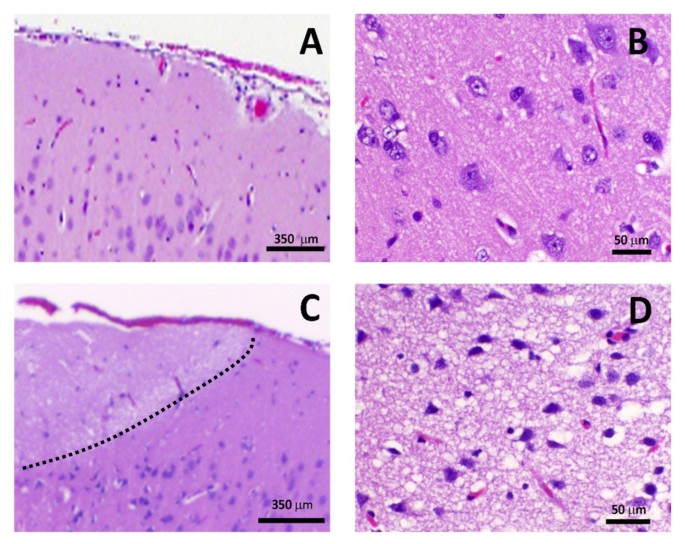

Микрофотографии гистологии глиобластомы головного мозга